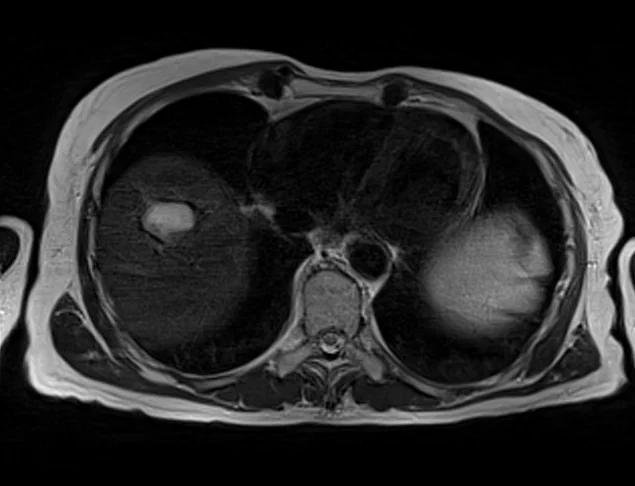

mrimaster

t2 4 - MRI